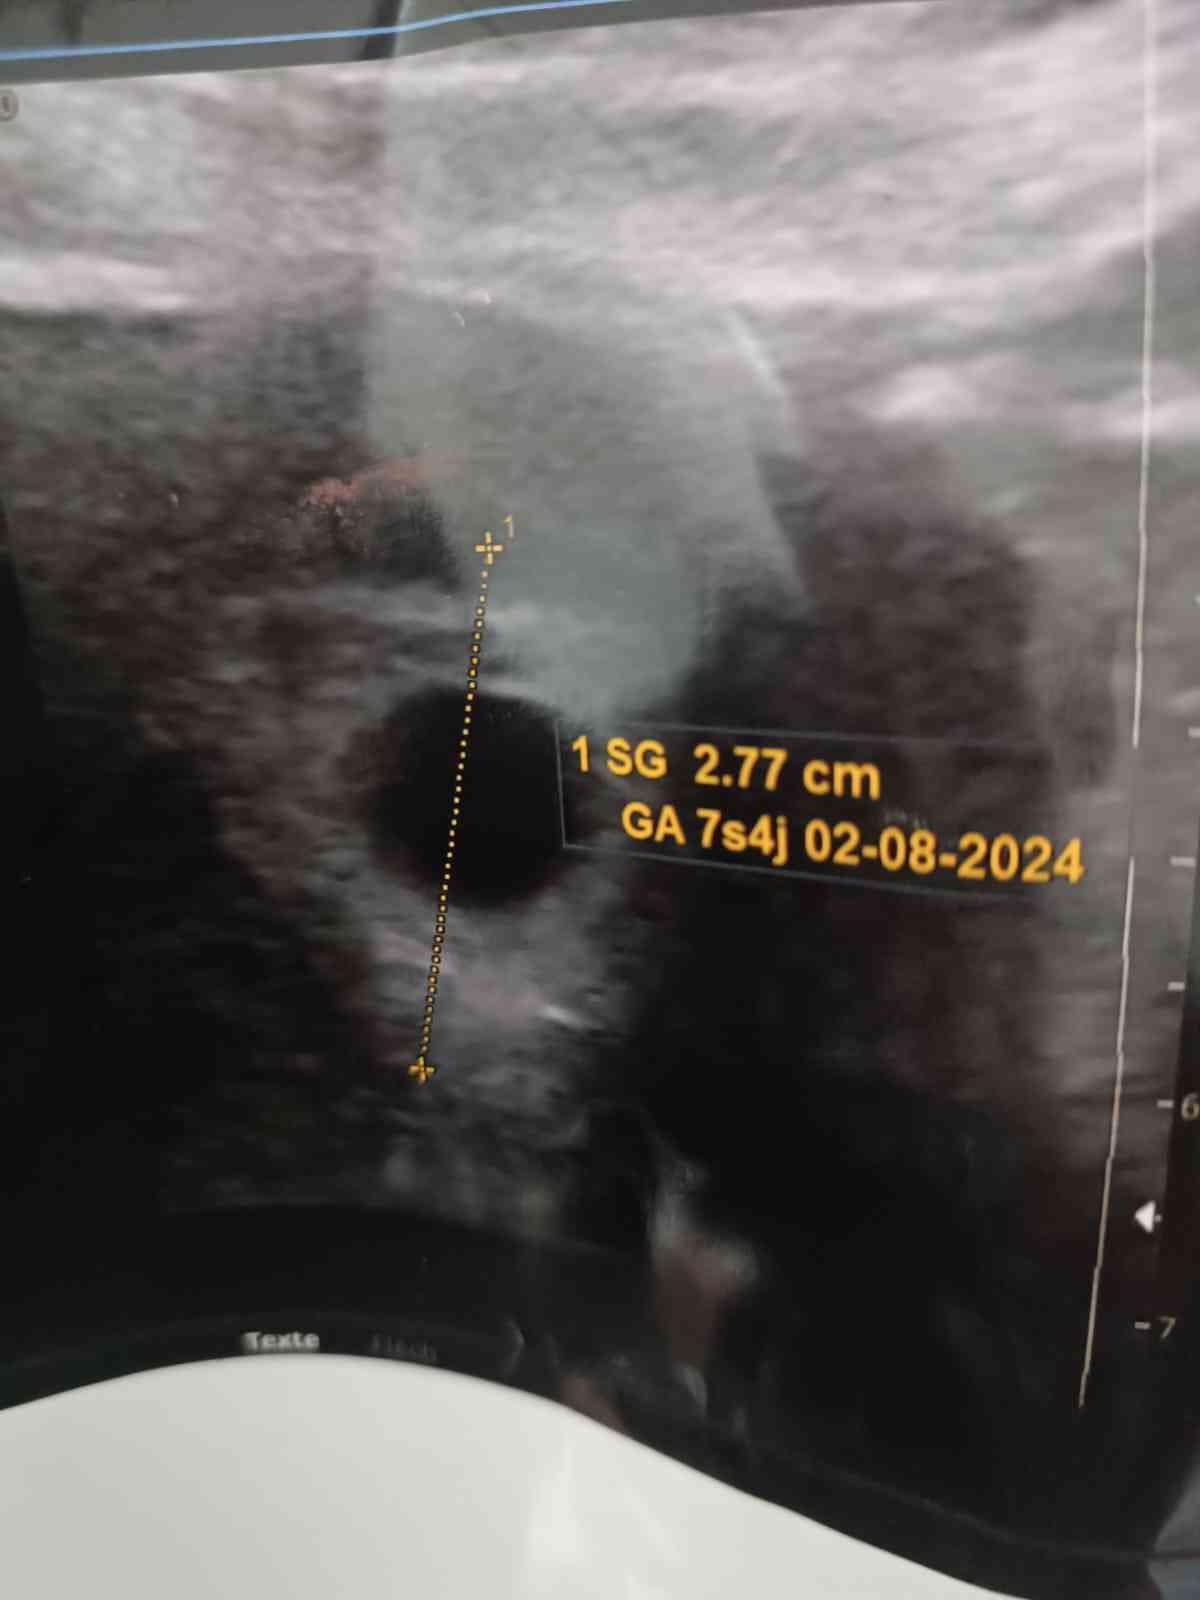

عمر الحمل و موعد الولادة